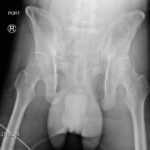

The initial radiograph of the pelvis shows an open-book pelvic fracture deformity with pubic symphyseal dislocation, left greater than right sacroiliac diastases, and fractures of the left superior and inferior pubic rami, right inferior pubic ramus, and left acetabular anterior column. The additional inlet and outlet radiographs of the pelvis after application of a pelvic binder also show an open book fracture with significant improvement of the widened pubic symphysis.